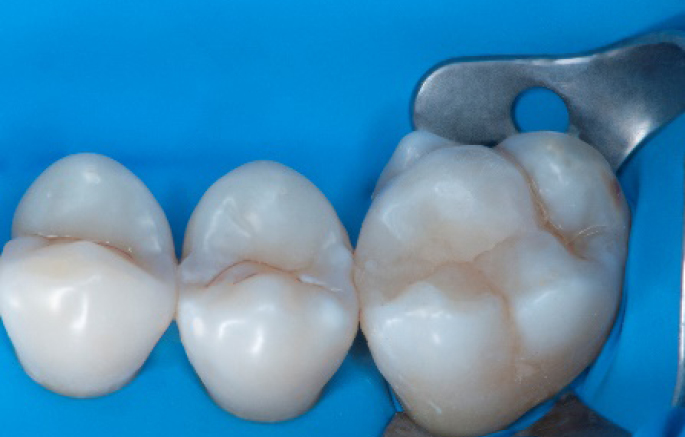

Step 12:

The situation after rubber dam removal.

Step 13:

Occlusal check

Step 14:

2 weeks control

After

Final situation 2 weeks after the filling. Great comfort and no sensitivity at all were reported by the patient.